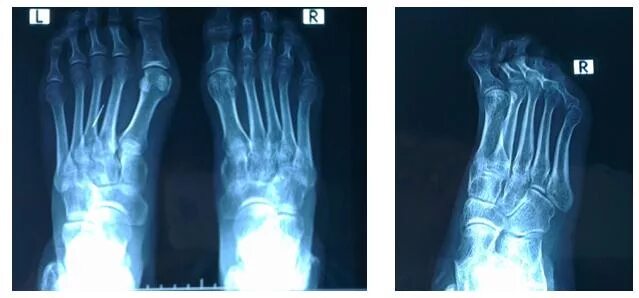

Деформация третьего